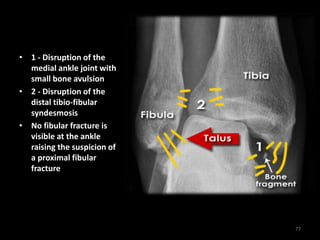

• 1 - Disruption of the

medial ankle joint with

small bone avulsion

• 2 - Disruption of the

distal tibio-fibular

syndesmosis

• No fibular fracture is

visible at the ankle

raising the suspicion of

a proximal fibular

fracture